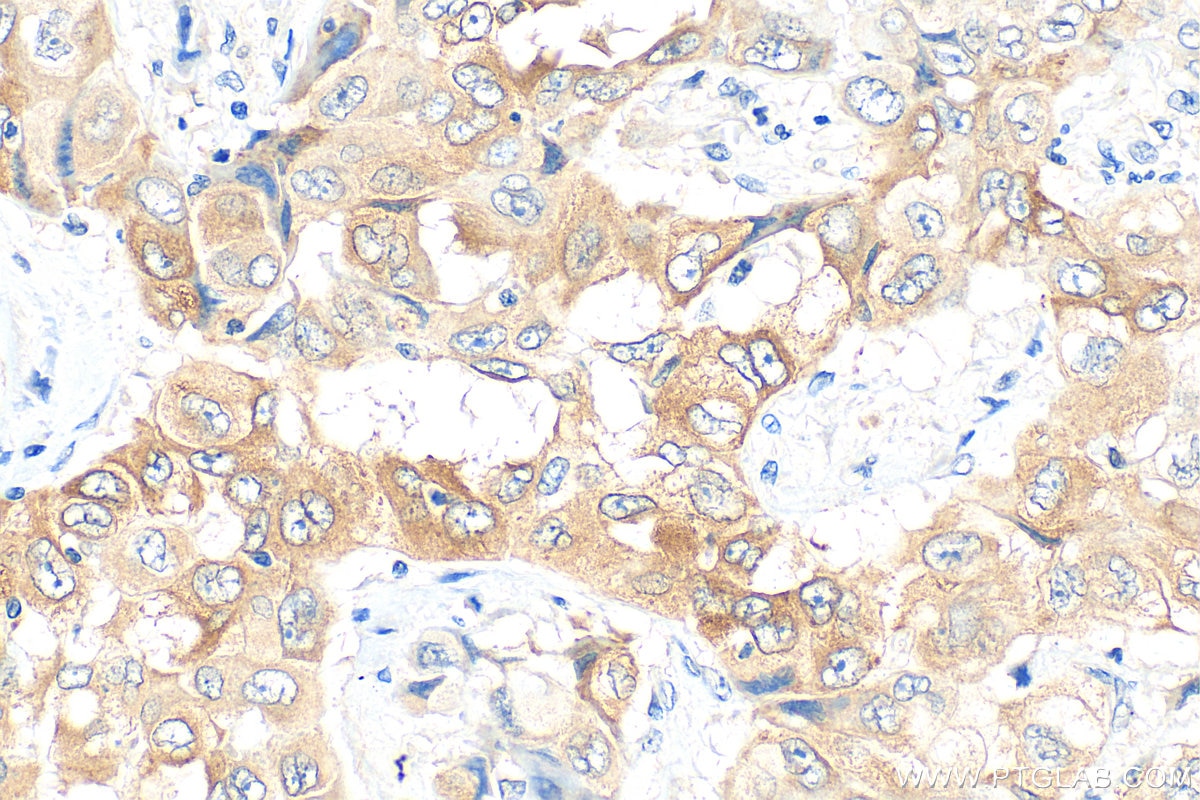

| Positive IHC detected in | human lung cancer tissue, human liver cancer tissue, mouse lung tissue Note: suggested antigen retrieval with TE buffer pH 9.0; (*) Alternatively, antigen retrieval may be performed with citrate buffer pH 6.0 |

| Immunohistochemistry (IHC) | IHC : 1:50-1:500 |